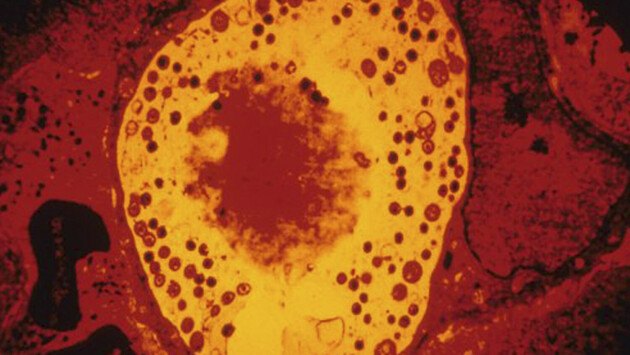

Анализ показал, что у пациентов с болезнью Альцгеймера в тканях сетчатки и головного мозга обнаруживались значительно более высокие концентрации хламидий. Это род грамотрицательных бактерий, виды которых относятся к облигатным внутриклеточным паразитам. Хламидии вызывают заболевания у человека, животных и птиц.

Чтобы разобраться в механизме, исследователи провели эксперименты на мышах. Они показали, что присутствие хламидий активирует хроническое воспаление, гибель нервных клеток и выработку бета-амилоида — токсичного для нейронов белка, накопление которого считается одной из центральных особенностей болезни Альцгеймера. В совокупности эти процессы ускоряли нейродегенерацию.